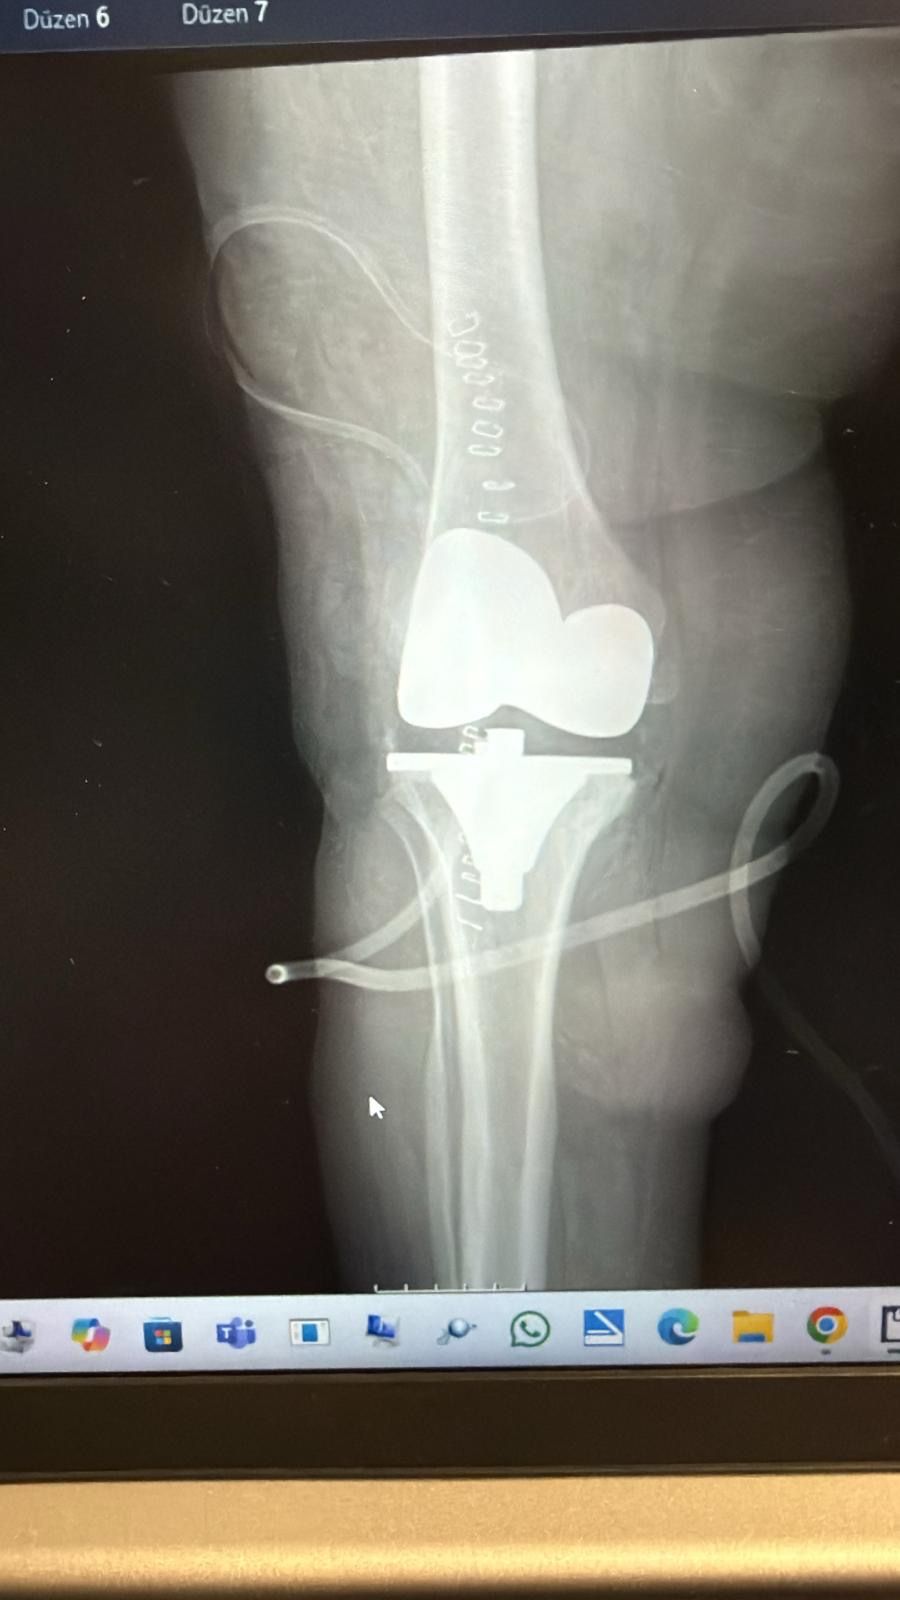

Moderator.az xəbər verir ki, İnönü Universiteti Turgut Özal Tibb Mərkəzində həyata keçirilən uğurlu əməliyyat zamanı Büyükbirerin dizindən 24 ədəd daşlaşmış şiş çıxarılıb. Uzun illər ağrıdan əziyyət çəkən və gəzə bilməyən Elif Büyükbirer çarəni Turgut Özal TibbMərkəzində tapıb. Aparılan ətraflı müayinələrdə xəstənin diz oynağında xəmirləşmiş dərəcədə kalsifikasiya, həm də nadir rast gəlinən “sinovialkondromatoz” adlı xəstəlikdən yaranmış çox sayda daşlaşmış şiş aşkarlanıb. Ortopediya və travmatologiya üzrə mütəxəssis prof. Dr. Reşit Sevimli tərəfindən həyata keçirilən əməliyyatda xəstənin dizindən 24 ədəd daşlaşmış şiş təmizlənib. Həmçinin eyni vaxtda total diz protezi də tətbiq edilib.

Prof. Dr.Sevimli əməliyyatın çox nadir bir hadisə olduğunu qeyd edib: “Elif xanımın dizində həm şiş, həm də kalsifikasiya mövcud idi. Bu iki halın eyni anda baş verməsinə çox nadır hallarda rast gəlinir. Diz oynağından "oynaq daşları"’ adlandırdığımız 24 ədəd kütlə çıxardıq. Daha sonra total diz protezi əməliyyatını da həyata keçirdik. Hazırda xəstəmiz rahat şəkildə gəzə bilir.”